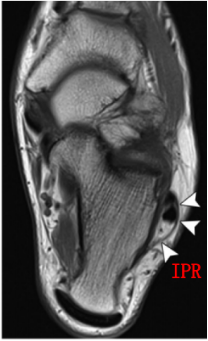

下支持带(IPR):前上方与伸肌支持带外侧根延续,后下方附着于跟骨前部外侧面。在跟骨滑车上下形成两个纤维管道固定肌腱于跟骨外侧壁。

MRI:能更清楚地显示软组织损伤情况,如支持带撕裂和腓骨肌腱半脱位。对于指导临床治疗及后期随访观察疗效具有重要参考价值。